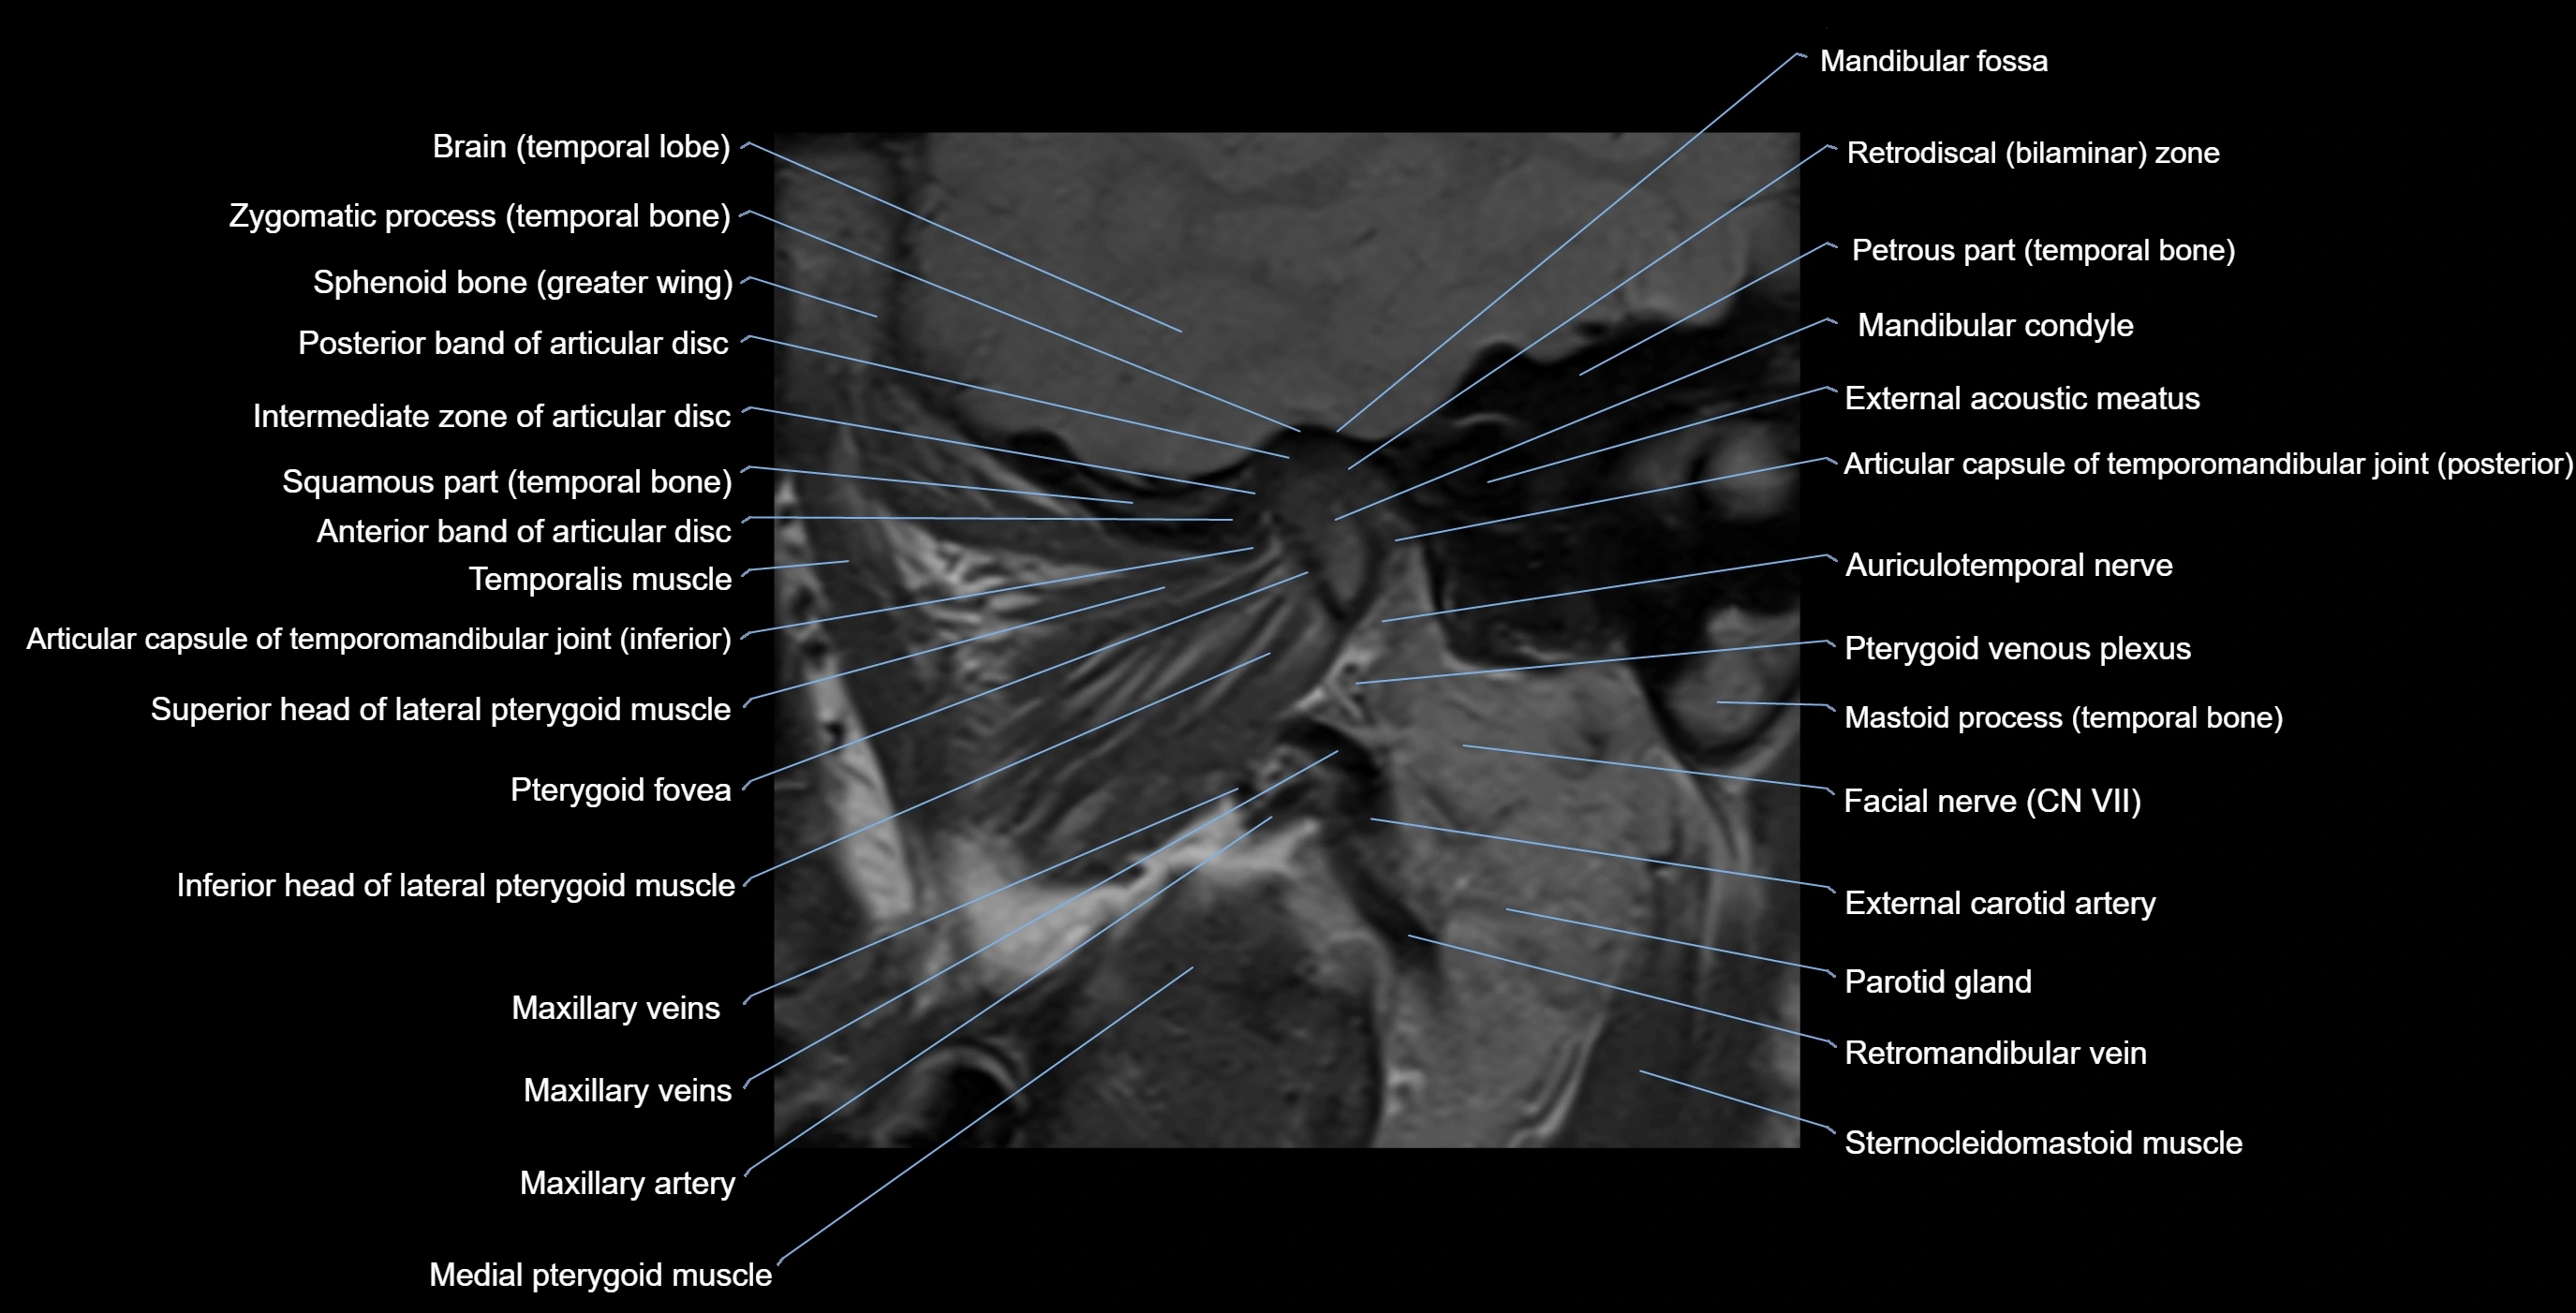

MRI appearance

T1-weighted images:

• Cortical bone: Low signal intensity

• Cancellous marrow: Intermediate to high signal depending on fatty content

• Teeth: Signal void structures

• Adjacent soft tissues: Normal gingiva and oral mucosa signal

T2-weighted images:

• Cortical bone and teeth: Low signal

• Marrow: Intermediate signal